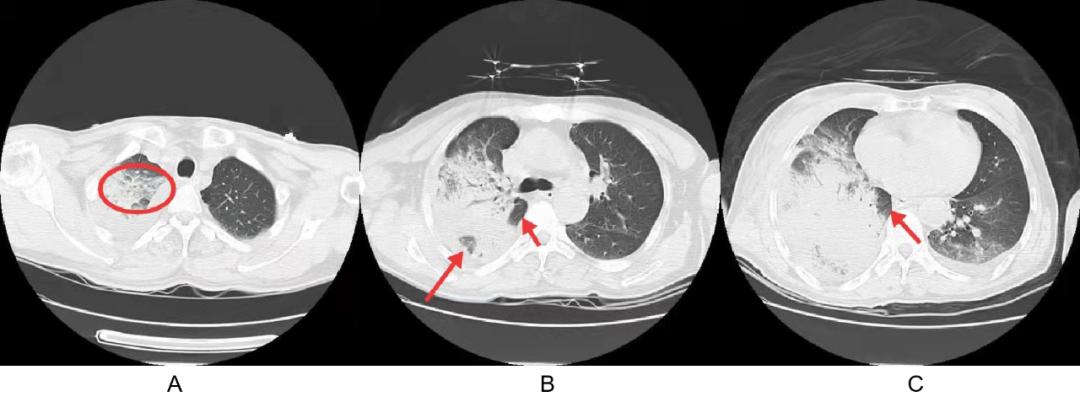

当地医院 2020-09-19 的胸 CT:

注: A :右肺上叶红圈内见叠瓦片征(发病在 24 小时内); B :右肺大片状阴影,病灶内及肺门处小叶闲置; C :靠近肺门小叶闲置。

叠瓦片征 :肺小叶内液体渗出,因重力原因位于肺小叶的下部,多个肺小叶同样表现,形似叠瓦片,最常见于肺泡性肺水肿,也可见于肺炎链球菌肺炎的充血水肿期、鹦鹉热衣原体肺炎早期、粘液腺癌等疾病。

肺泡灌洗液培养回报:大肠埃希菌。但观察影像其实不支持大肠埃希菌肺炎,大肠埃希菌肺炎很少出现本例这样大片实变影而又无空洞的表现;美罗培南治疗无效也进一步证明该病例不是大肠埃希菌肺炎,而符合肺炎链球菌肺炎,我会诊建议停用美罗培南,同时查肺泡灌洗液 NGS。但该主管医生并没有停美罗培南,但也用上了大剂量青霉素,复查胸部 CT 病灶吸收。后续肺泡灌洗液 NGS 回报:链球菌属 609 条,其中肺炎链球菌 48 条、轻型链球菌 326 条(此前已用过青霉素治疗)。